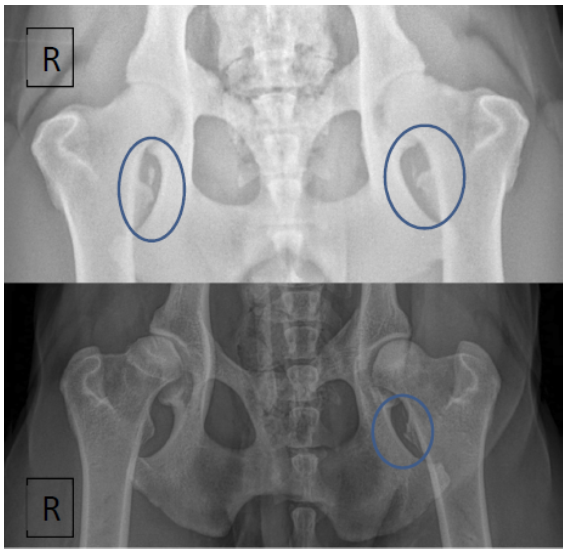

Methods: Medical records of 73 agility performance canines that underwent musculoskeletal ultrasound evaluation of bilateral iliopsoas muscle groups were retrospectively reviewed. Data included signalment, previous radiographic findings, and ultrasound findings. A 3-tier grading scheme for acute strains was used while the practitioner also evaluated for evidence of chronic injury and bursitis.

Results: The majority of pathologies were localised to the tendon of insertion, with the majority being low grade I-II strains (80.8%). Tendon fibre disruption (71.2%) and indistinct hypoechoic lesions (91.8%) were the most common of acute changes noted. Hyperechoic chronic changes were noted in 84.9 percent of cases. Acute and chronic changes were commonly seen together (62.8%).

Conclusion: Diagnostic musculoskeletal ultrasound was used to identify lesions of the iliopsoas tendon consistent with acute and chronic injury, as well as identifying the region of pathology. The majority of agility performance dogs had low grade acute strains based on the tiered system, with mixed acute and chronic lesions being noted frequently.